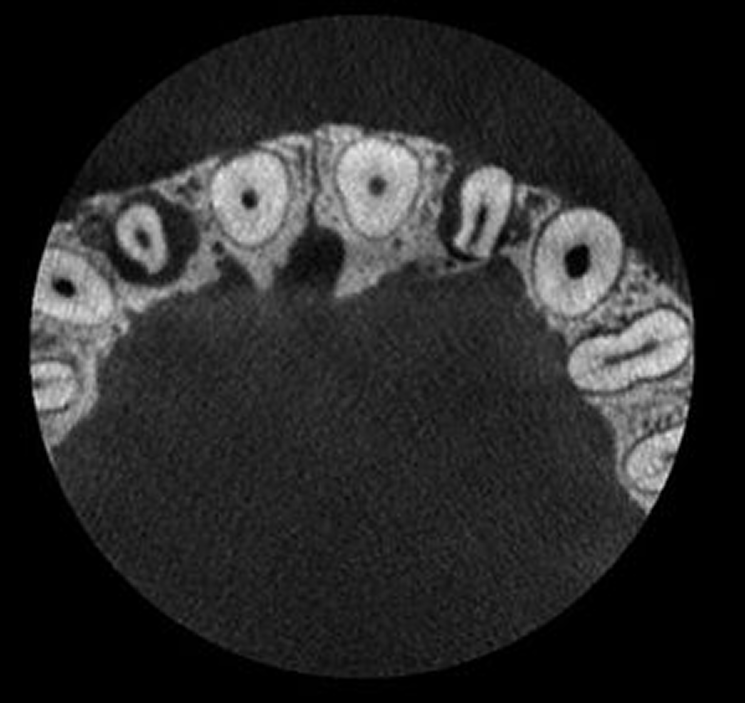

Cutting Edge Endodontic Imaging

Noise is often inherent to endodontic imaging due to the high resolution required to capture small details.

The 3D endodontic imaging mode for Planmeca Viso combats this issue and allows capturing clear and smooth CBCT images that are perfect for endodontics. In addition to new unit deliveries, the new imaging mode is available for existing units with a software update.